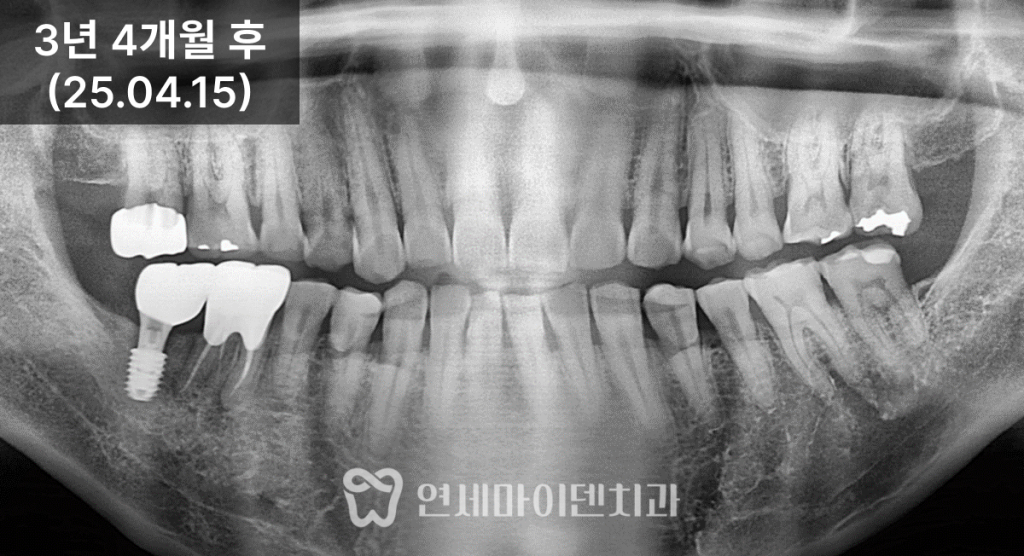

앞쪽 어금니의 흔들림도 눈에 띄게 줄어들었습니다.3년 경과 후 결과

치료 후 3년이 지난 현재까지도

임플란트, 보존한 자연치

모두 안정적으로 유지되고 있습니다.초기에는 뼈가 절반밖에 남지 않았던 부위가

뼈이식 후 건강한 높이로 회복되었고,

그 결과 임플란트 하나가

옆 자연치의 수명까지 함께 늘려준 셈이 되었습니다.

임플란트는 단순히

“비어 있는 자리만 채우는 치료”가 아닙니다.어디에 심는지,

뼈이식을 어디까지 하는지에 따라

주변 자연치의 예후까지 달라질 수 있습니다.이 케이스처럼,

뽑지 않아도 될 치아는 살리고

임플란트를 통해 주변 뼈를 함께 복원한다면전체 교합 안정성과 장기 예후는

훨씬 좋아질 수 있습니다.임플란트가 필요한 상황이라도,